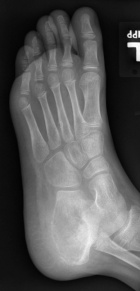

7 year old male who has had a six month history of left heel pain which was first noted with difficulty putting on his socks.

PMX- neurofibromatosis & scoliosis. Left foot pain is sharp, severe at times, constant in nature, worse with activity. Family describes the discomfort as worsening. It is made better with rest. He has no other history of trauma.

Zoom image: Radiological image Radiological image.